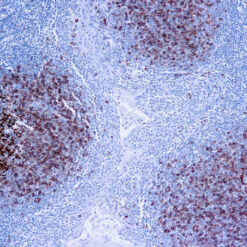

Leukocyte Common Antigen (LCA)/CD45

CD45R, also designated CD45 and PTPRC, has been identified as a transmembrane glycoprotein, broadly expressed among hematopoietic cells. Multiple isoforms of CD45R are distributed throughout the immune system according to cell type. These isoforms arise because of alternative splicing of exons 4, 5, and 6. The corresponding protein domains are characterized by the binding of monoclonal antibodies specific for CD45RA (exon 4), CD45RB (exon 5), CD45RC (exon 6) and CD45RO (exons 4 to 6 spliced out). The variation in these isoforms is localized to the extracellular domain of CD45R, while the intracellular domain is conserved. CD45R functions as a phosphor-tyrosine phosphatase. Antibody to CD45 is useful in differential diagnosis of lymphoid tumors from non-hematopoietic undifferentiated neoplasms.

| Positive Control Tissue | Tonsil |